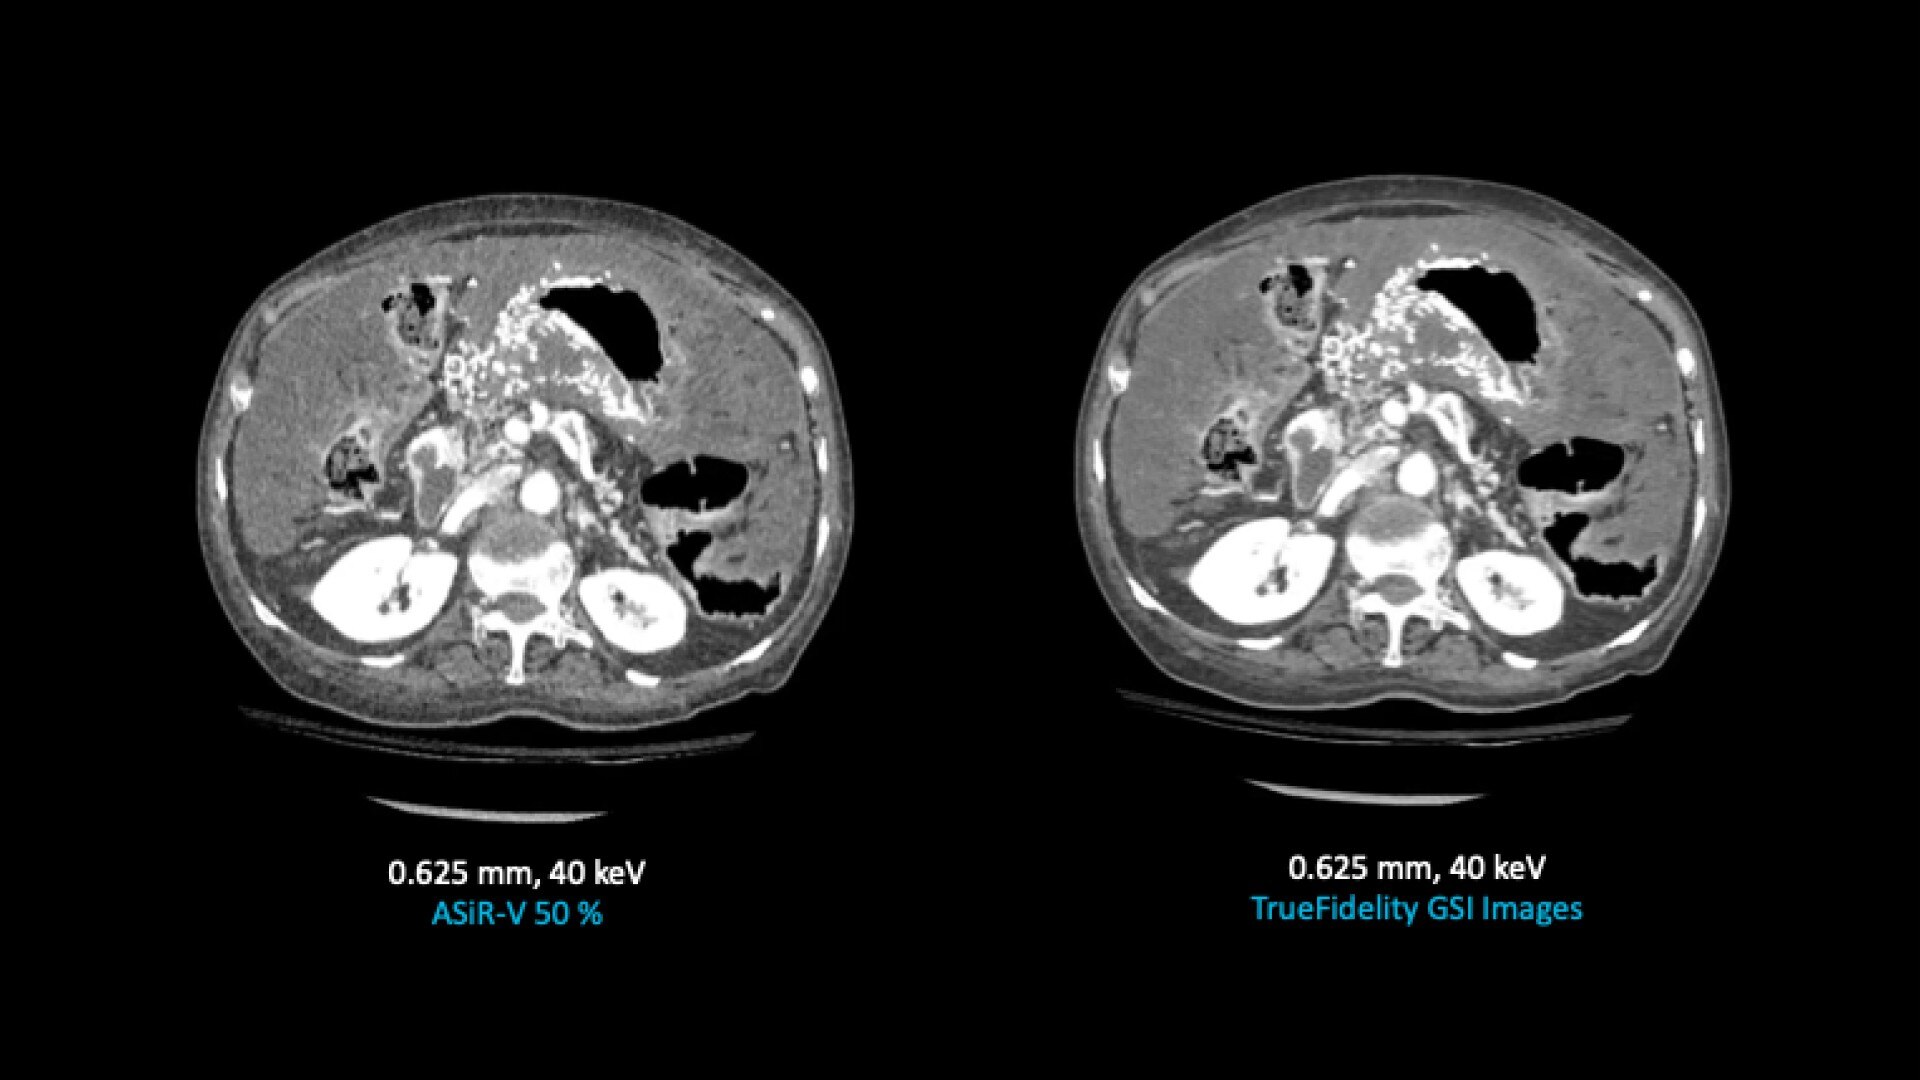

TrueFidelity for GSI now brings the potential to substantially reduce the image noise in all spectral image types

From virtual monochromatic images to material image pairs and virtual non-contrast images, with and without metal artifact reduction. Specifically, reducing the image noise inherent with low keV images resolves one of the traditional technical challenges in adopting more dual-energy protocols across the full patient population.